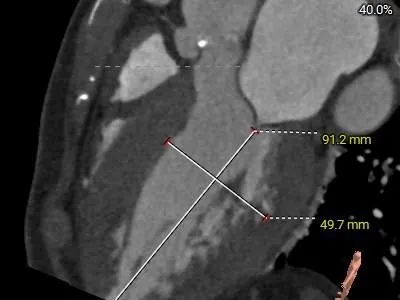

STJ 26.3mm

高16.7mm

AAO

33.4mm

L-30.6mm R-27.5mm

N-29.5mm

-

三叶瓣,RL/RN高位纤维融合,瓣环偏大

瓣环直径约20.1mm,直筒型流出道

瓣叶增厚,中度钙化

外周入路评估

外周血管内径充足,无明显钙化,腹主动脉轻微迂曲

47°非横位心